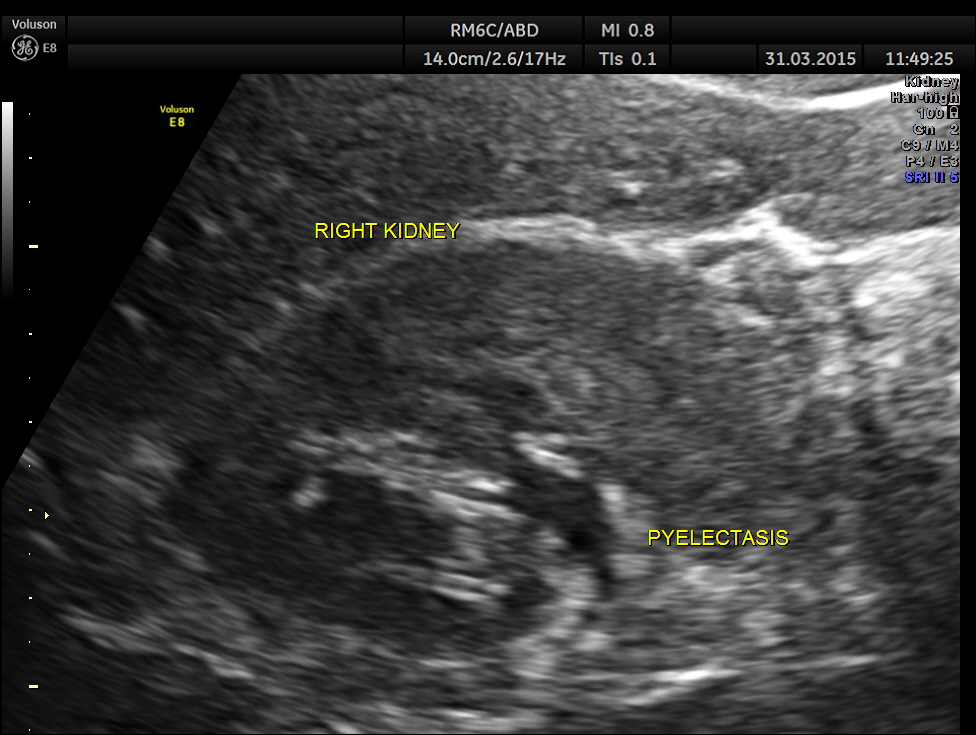

Ultrasound showed the following.

Right kidney shows mild pelvi calyceal dilatation.

Can we jump to the diagnosis of ureteric calculus now ?

Is there an incongruity between the size of the calculus and the ” ureteric dilatation ” and the pelvi calyceal dilatation ?

Careful attempt to establish any continuity of the dilated ” tube ” to the ureter or dilated pelvis , showed that the dilated structure was separate from the right ureter .